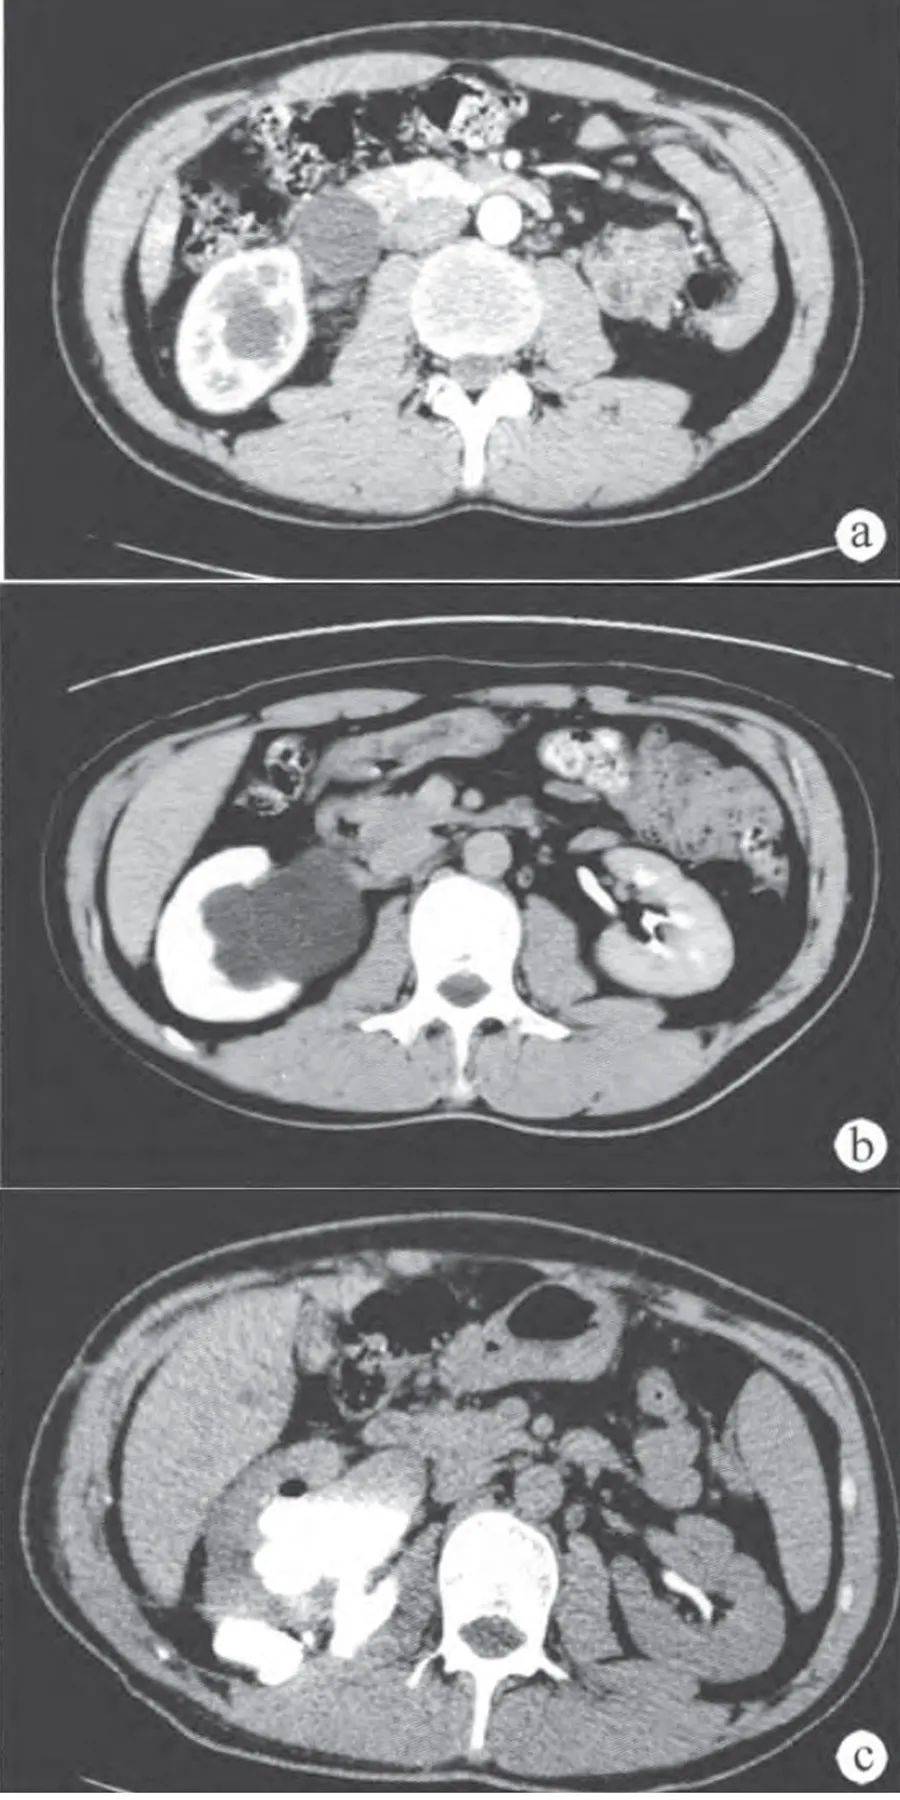

肾盏憩室:肾囊肿的鉴别诊断_输尿管_肾盂_扫描

肾盏憩室是指位于肾脏内的含有尿液的囊性结构,内衬为移行上皮,周围有